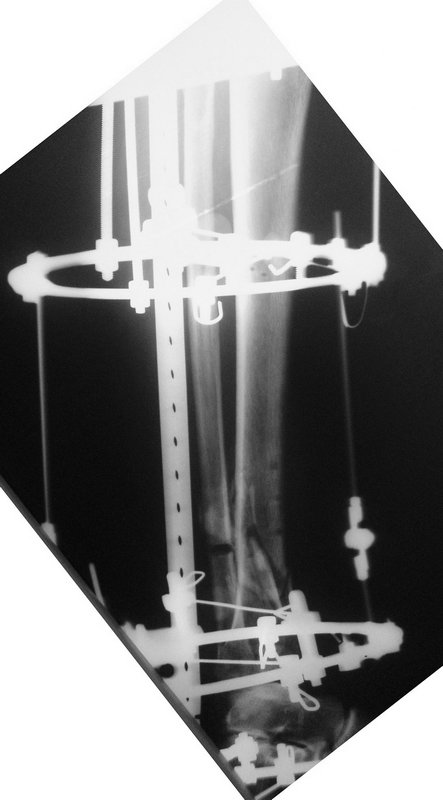

19 апреля  убрали через проколы пластину с винтами, пересекли fibula,

наложили аппарат.

Немного потянули по оси, убрали вальгус, ротацию. 22 апреля (на 3-е сутки)

заштифтовали окончательно. 29 апреля выписали из отделения. На все ушло 10

дней.

Вложение не в текстовом формате было извлечено…

Имя     : ilizar1.jpg

Тип     : image/jpeg

Размер  : 49761 байтов

Описание: отсутствует

Url     : http://weborto.net:8080/pipermail/ortho/attachments/20110817/7ada23a0/attachment-0010.jpg